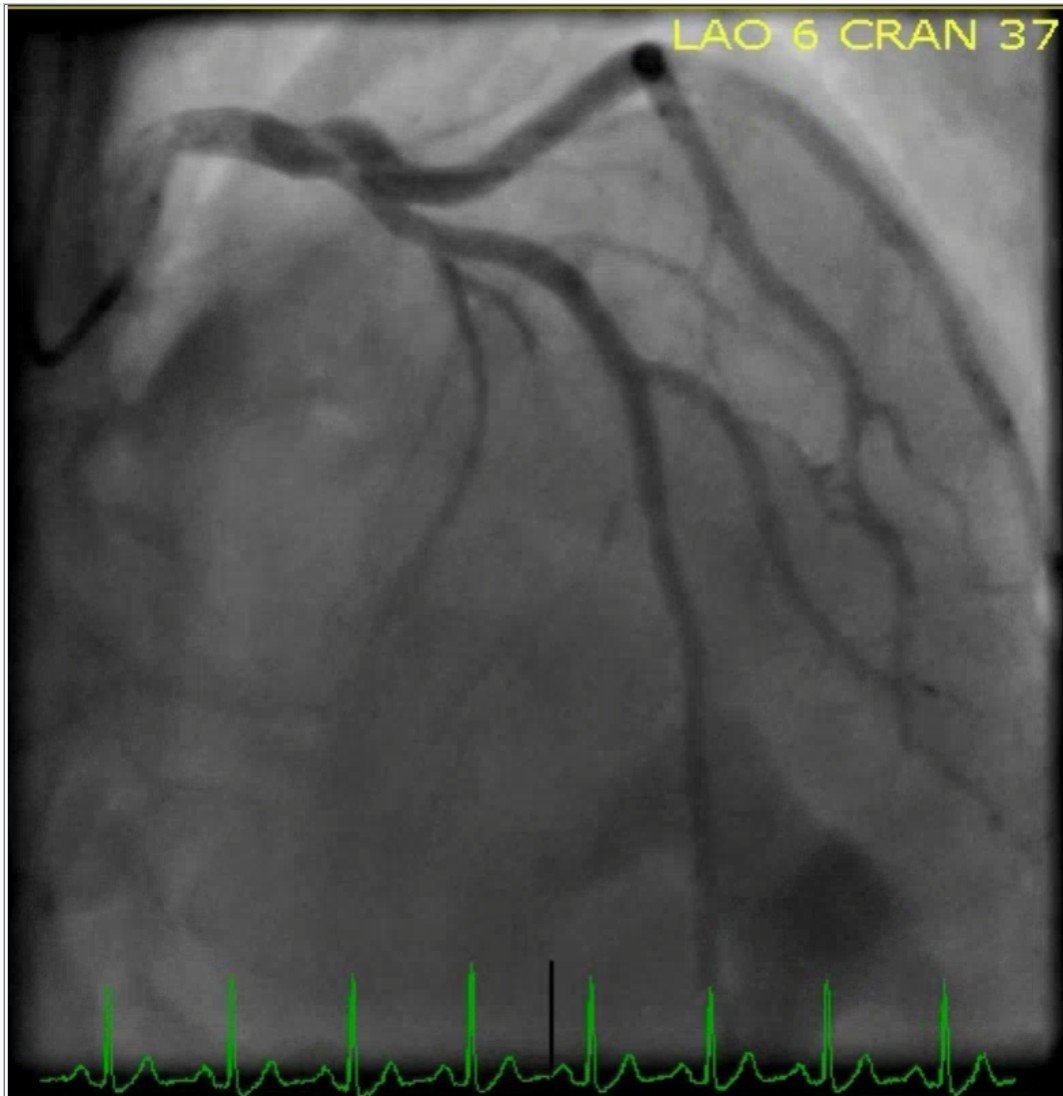

The cardiac catheterization revealed a thrombotic occlusion of the proximal to mid LAD (100% in-stent restenosis of the previously placed bare-metal stent). The patient underwent successful placement of one drug eluting stent with restoration of TIMI 3 flow. Here are the images from the cardiac cath:

Mid to distal-LAD in-stent stenosis with 100% occlusion and TIMI flow 0

LAD post-DES placement with TIMI 3 flow

The amount of territory supplied by this vessel becomes obvious here (and goes on for a few more frames below this still). None of this territory was perfused until this point.